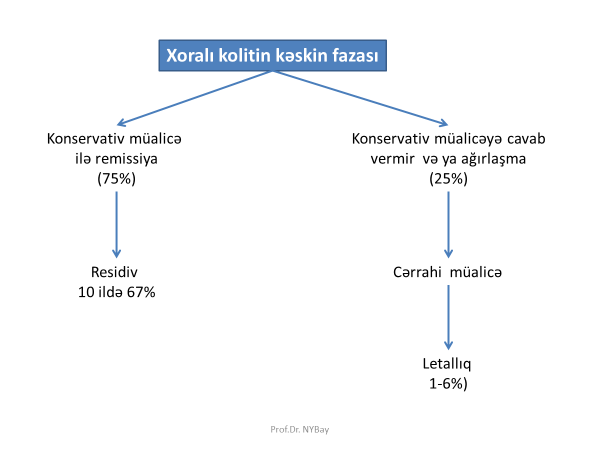

Xoralı kolitdə əməliyyata göstərişlər hansılardır?

Toksik megakolon, massiv qanaxma, uşaqlarda inkişafdan qalma, steroid müalicəsi fonunda perforasiya, konservativ müalicənin effekt verməməsi